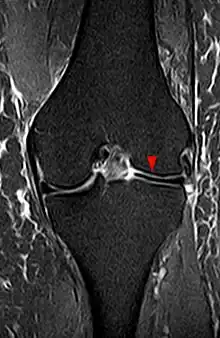

Le type III de la classification de Watanabe est invisible en imagerie[2]. Les types I et II se caractérisent en IRM par une augmentation de l’épaisseur du ménisque avec augmentation du nombre de coupes sagittales sur lesquelles une continuité entre corne antérieure et postérieure est visualisée[2]. Le nombre de coupes dépendant de leur épaisseur, on peut choisir comme seuil trois coupes de 5 mm[1],[2]. Dans le plan coronal, une largeur méniscale supérieure à 15 mm a été proposée comme critère diagnostique d'un ménisque discoïde[1].La radiographie conventionnelle est peu efficace, pouvant montrer un élargissement aspécifique de l’interligne articulaire tibia-fémoral[1],[2]. En cas de fissure méniscale, la sémiologie n’est pas différente de celle observée en cas de ménisque normal[2].